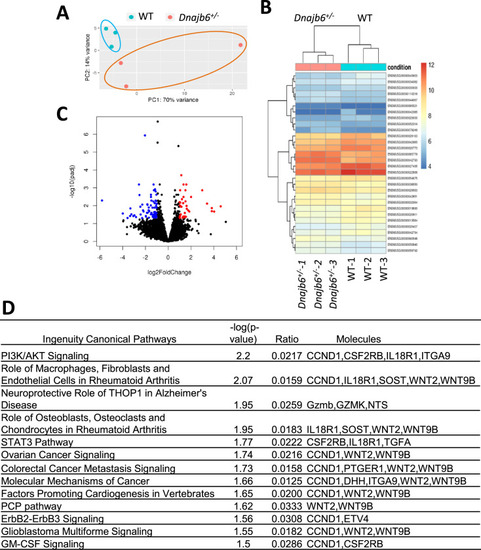

RNA sequencing identifies transcriptome changes in the Dnajb6+/- mice atrium. (A) Principal component analysis (PCA) reveals the variance in transcriptome distribution in the Dnajb6+/- mice and WT controls at 6 months. Each point represents the projections of individual hearts onto principal component (PC). (B) Heatmap of genes differentially expressed in the Dnajb6+/- mice and WT controls. Each column represents an individual replicate and there are 3 replicates per group. Each row represents an individual gene. The color bar represents relative expression of log-transformed, normalized counts with upregulated genes shown in red and downregulated genes in blue. (C) Volcano plot shows magnitude and significance of genes that altered in distribution in the Dnajb6+/- mice and WT controls. Genes that significantly downregulated in the Dnajb6+/- mice are plotted in blue (left) and upregulated are plotted in red (right). (D) Ingenuity Pathway Analysis (IPA) of differentially expressed genes in the Dnajb6+/- mice and WT controls. Signaling pathways are organized in the order of significance as –log10 of P value. |